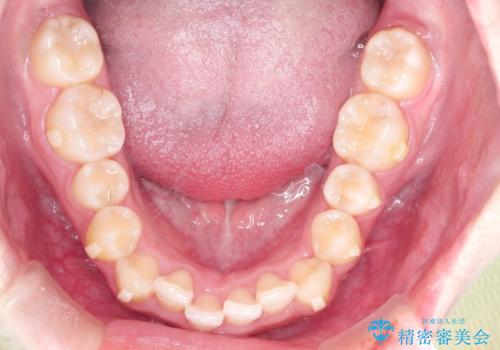

インビザラインでの前歯のガタガタの矯正

- 上下の前歯のがたつきを主訴に来院されました。

歯と歯の間をわずかに削りスペースを作り、インビザラインにて矯正治療を行うこととしました。

使用時間を守っていただけたので、スムーズに矯正を終了することができました。